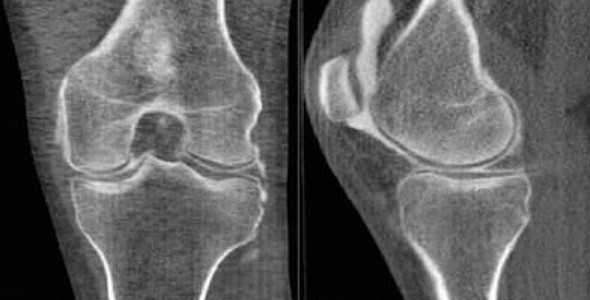

Компьютерная томография колена

КТ колена

С помощью компьютерной томографии визуализируют нарушения связочного аппарата, костных суставных поверхностей, гиалинового хряща, синовиальной оболочки и капсулы сочленения. Ограничение подвижности и боль возникают чаще при травмах, воспалительных и дегенеративных патологиях.

КТ коленного сустава позволяет диагностировать хондромаляции (разрушение хряща), повреждения менисков, разрывы крестообразных связок. В результате контрастной процедуры выявляют онкологические процессы, заболевания сосудов, липоартрит и пр.